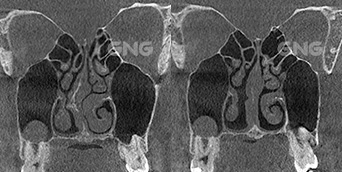

코막힘으로 내원하셨습니다. 코막힘 원인을 파악한 후비밸브 재건술, 비중격 재건술,하비갑개 절제술을함께 진행하신 분입니다. CT 사진을 보면 수술 전후의 변화를극명하게 확인하실 수 있는데요. 수술 전후 사진으로 비교했을 때,비강의 양쪽의 넓이가 비슷해지는 것이가장 이상적인 수술 결과입니다. <코막힘 원인> 수술 전 CT사진에서 뼈 부분이 왼쪽으로 치우쳐있고,왼쪽의 비강이 완전히 막혀있는데요. 위쪽 . . .